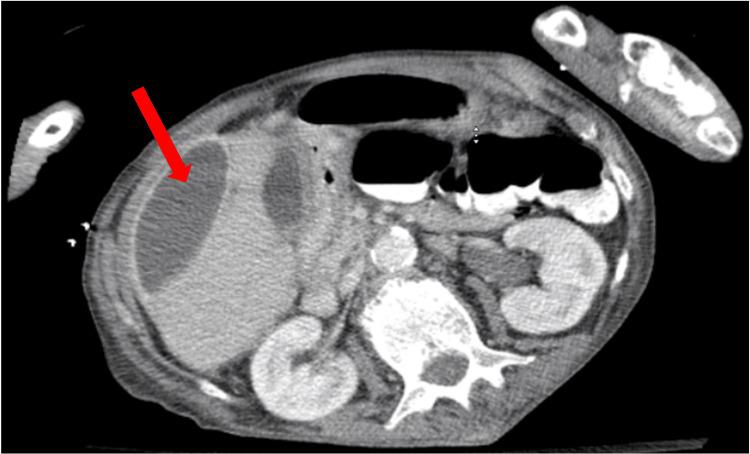

This is the case of a 65-year-old female patient with chronic obstructive pulmonary disease (COPD) who presented following a fall and was found to have a humeral fracture. Initial evaluation showed sepsis of unknown origin, leukocytosis, and elevated inflammatory markers. Persistent abdominal pain prompted imaging studies, which showed multiloculated intra-abdominal abscesses. Ultrasound-guided drainage yielded . Antibiotics, along with percutaneous drainage, resulted in a good clinical response. Follow-up imaging revealed a decrease in the abscess size, with no evidence of a fistula. This case highlights the diagnostic challenges of intra-abdominal abscesses and the importance of timely imaging in patients presenting with sepsis and nonspecific symptoms.

这是一名65岁患有慢性阻塞性肺疾病(COPD)的女性患者的病例,她在跌倒后就诊,被发现有肱骨骨折。初步评估显示有不明原因的脓毒症、白细胞增多和炎症标志物升高。持续的腹痛促使进行影像学检查,结果显示有多处腹腔内脓肿。超声引导下引流取得了……抗生素联合经皮引流产生了良好的临床反应。后续影像学检查显示脓肿大小减小,没有瘘管的迹象。该病例突出了腹腔内脓肿的诊断挑战以及对出现脓毒症和非特异性症状患者进行及时影像学检查的重要性。